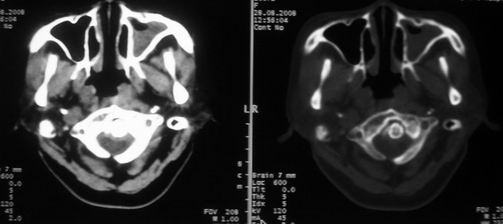

女,55岁,右侧颌下肿物3年。

右侧胸锁乳突肌后方软组织密度肿块,界限清楚。多考虑:血管源性肿瘤!

鼻咽左侧壁增厚,呈结节样突入鼻咽腔内,左侧咽隐窝消失,须考虑鼻咽癌可能,建议鼻咽纤维镜检查以明确诊断。

至于右侧颌下间隙的结节影,如果不考虑病史的话,可以诊断为淋巴结转移。但是结合病史“右侧颌下肿物3年”,又不象淋巴结转移了。建议ct增强扫描明确结节与右侧颌下腺的关系,或者穿刺活检定性。

右侧胸锁乳突肌内侧略低密度结节,应该是静内静脉而不是淋巴结。